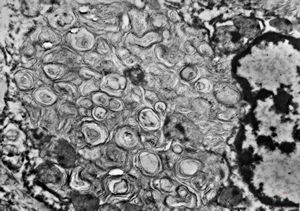

myelinoid inclusion

M,54y. | periodic nematosome-like intracytoplasmic configuration in an unclassified peritoneal tumor